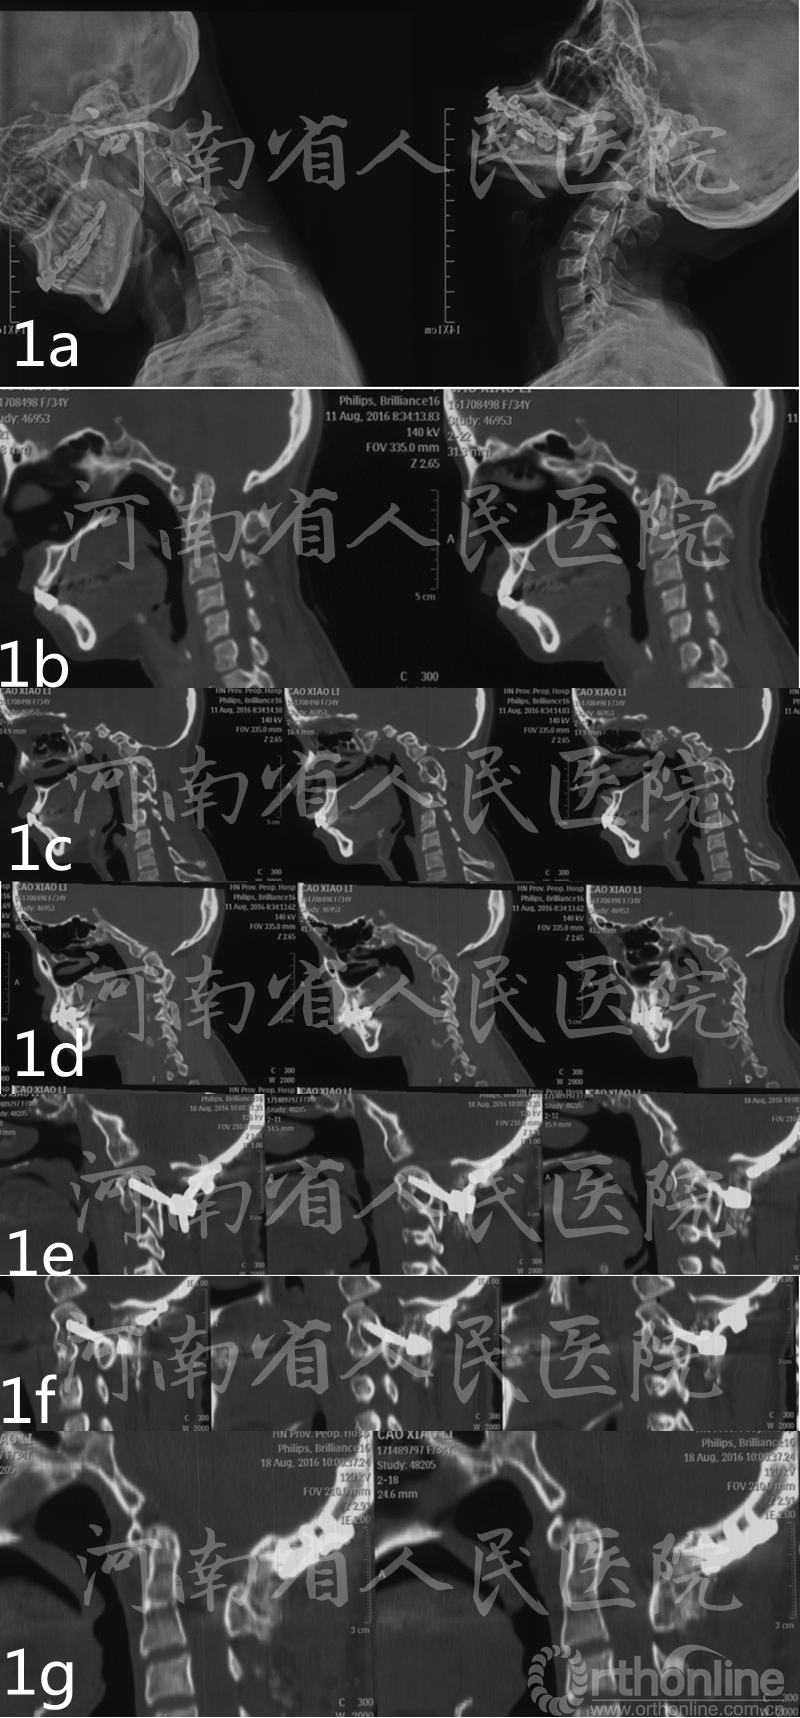

图1 患者女性,33岁,寰枕融合,颈2、3融合,寰枢椎不稳 a术前X线显示寰枢椎过伸位复位,过屈位脱位 b 术前矢状位CT示ADI增大 c术前矢状位CT示枢椎右侧椎弓根发育不良d术前矢状位CT示枢椎左侧椎弓根发育不良e 术后矢状位CT示枢椎右侧椎弓根钉为“in-out-in”三皮质螺钉 f术后矢状位CT示枢椎左侧椎弓根钉为“in-out-in”三皮质螺钉 g术后6月CT示骨性融合,复位无丢失

患者均获得随访8-20个月,平均12个月,术后6个月影像学检查见植骨融合,无内固定松动,断裂发生。术后7d及末次随访VAS评分分别为(1.13±0.72)分,(1.07±0.81)分,较术前明显减轻;术后7d及末次随访时JOA评分分别为(12.9±1.8)分,(13.8±2.1)分,与术前比较明显改善。(表1)(图1、2)